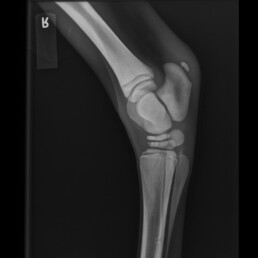

In der röntgenologischen Untersuchung der Tarsi und Carpi wurde eine hypoplastische Ossification Grad 2-3 festgestellt (schwach entwickelte Verknöcherung).

Abb. 4 – 90° rechte Hintergliedmaße: inkomplette Ossifikation der Tarsalknochen Grad 2

Abb. 5 -90° rechte Hintergliedmaße: inkomplette Ossifikation der Tarsalknochen Grad 2